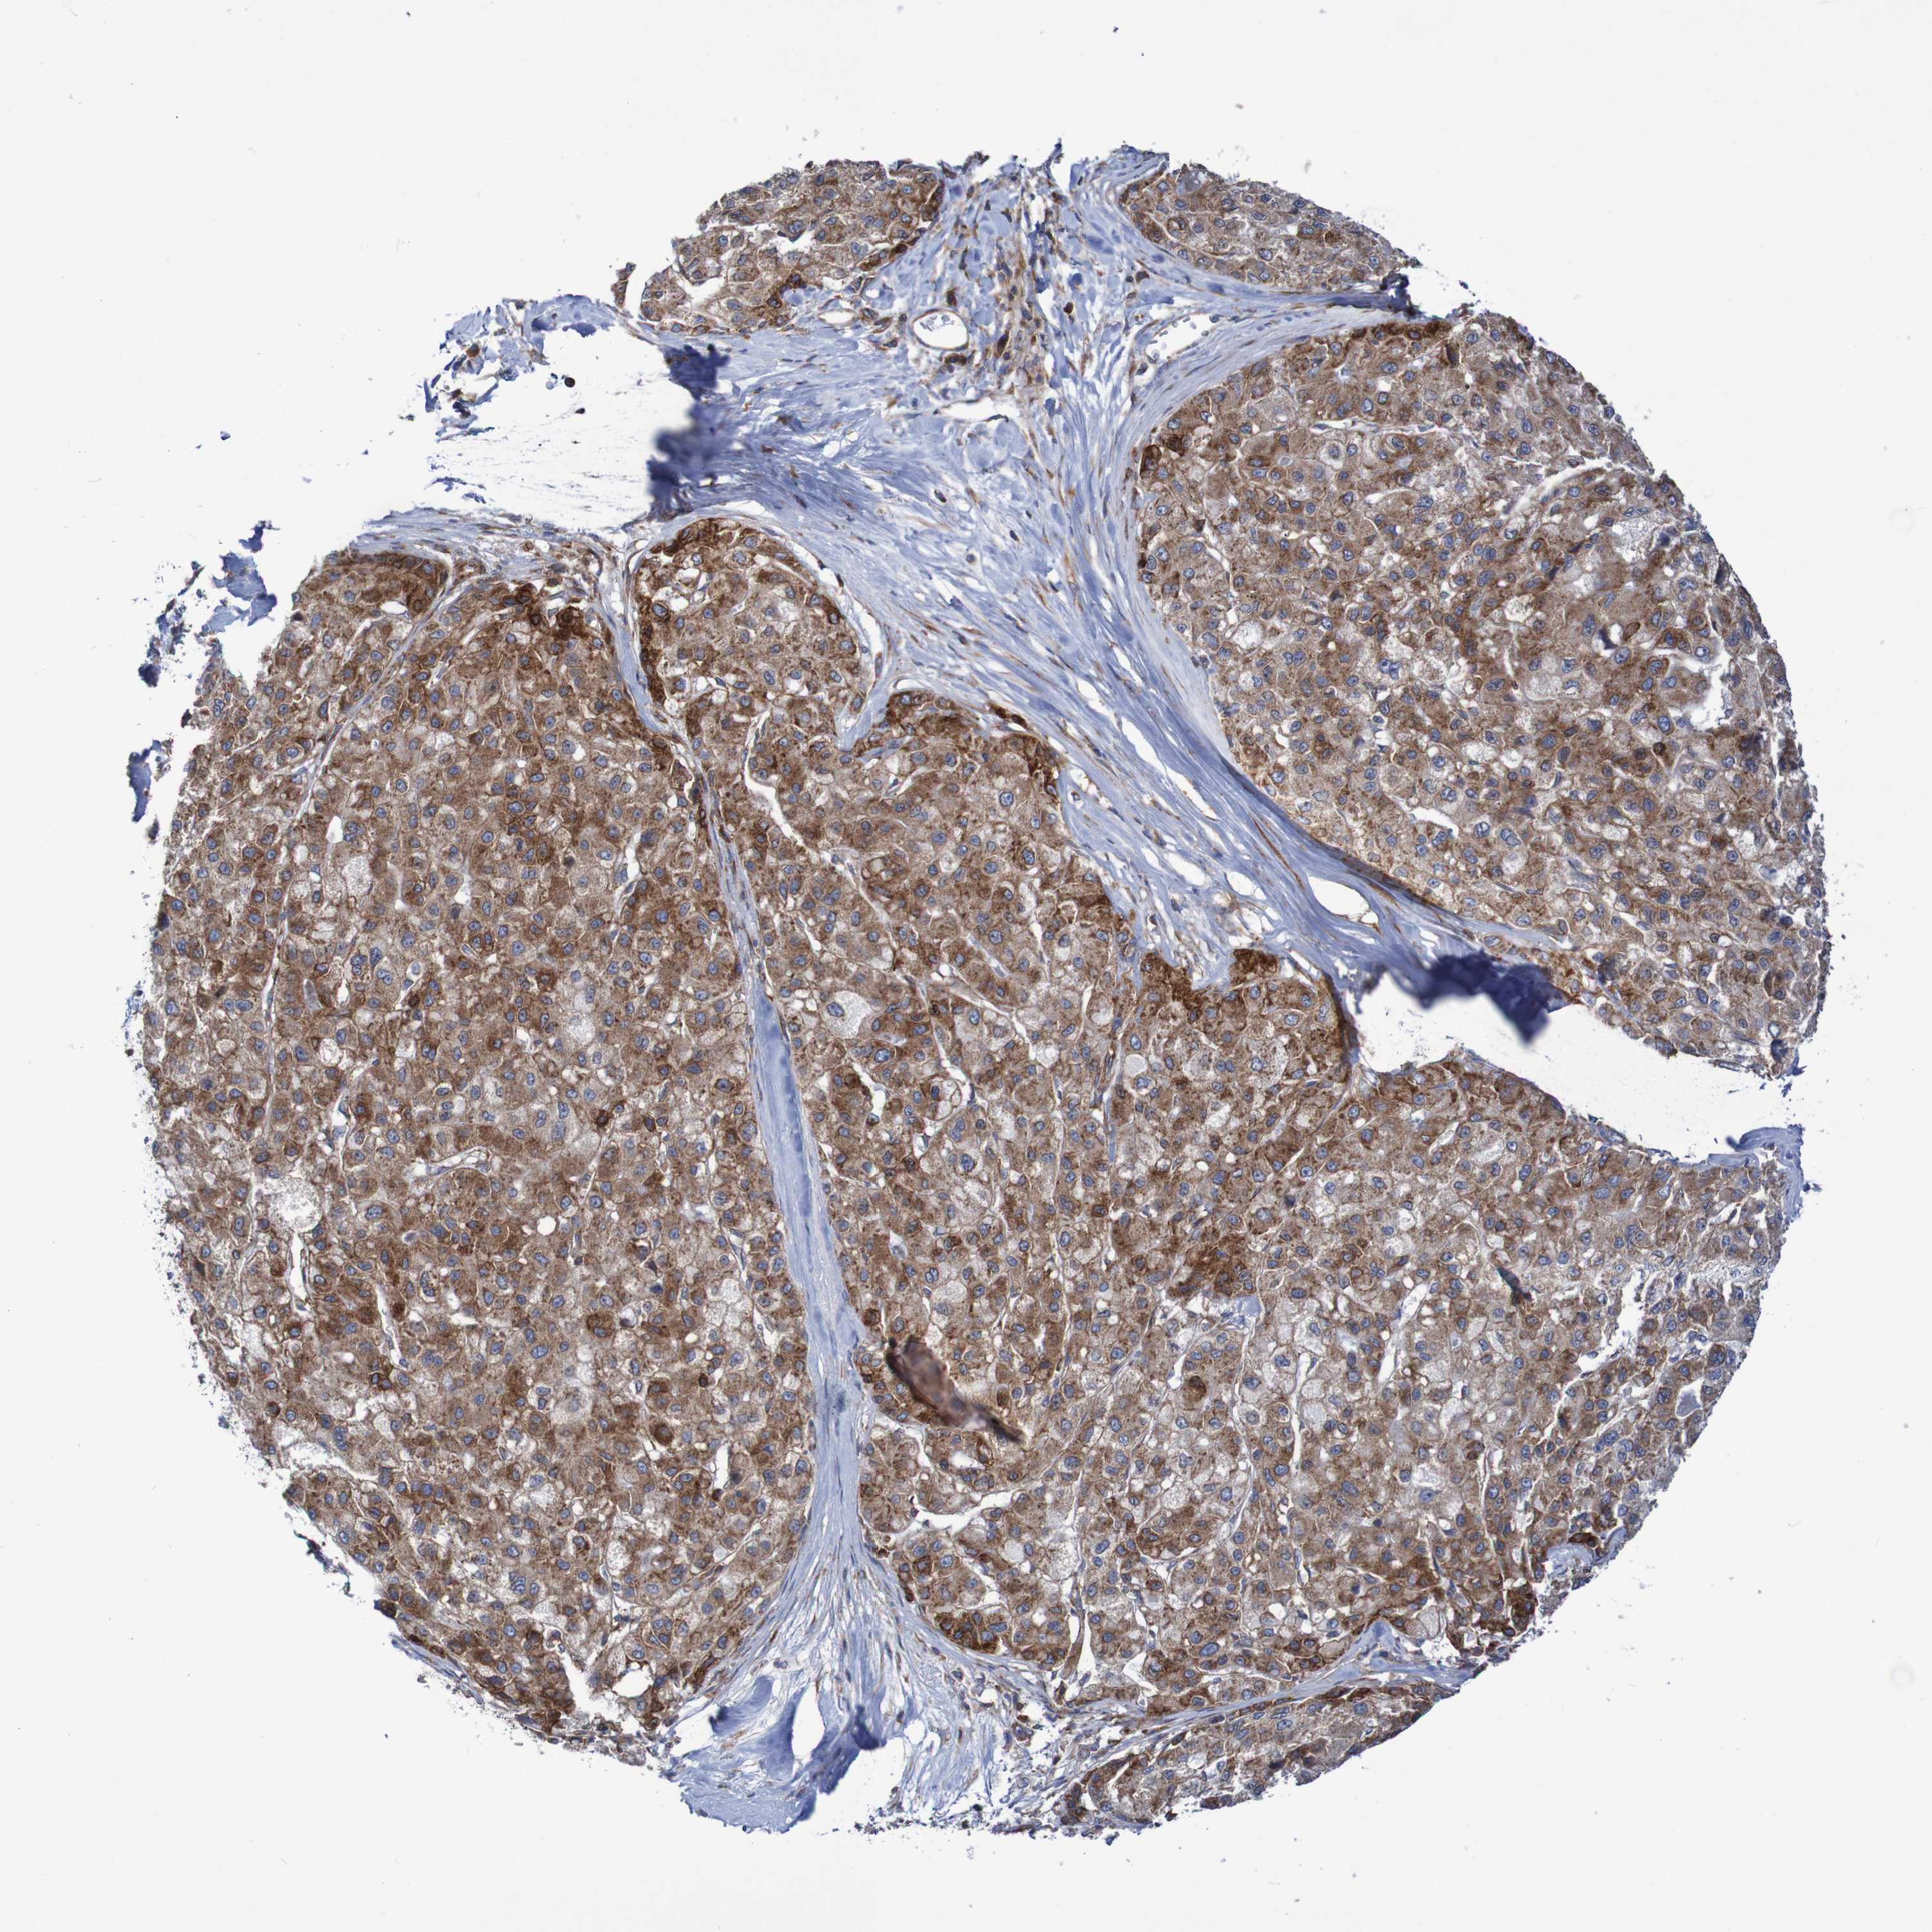

LIVER CANCER - Protein expressioni

A mouse-over function shows sample information and annotation data. Click on an image to view it in a full screen mode. Samples can be filtered based on level of antibody staining by selecting one or several of the following categories: high, medium, low and not detected. The assay and annotation is described here.

Antibody stainingi

Antibody staining in the annotated cell types in the current human tissue is reported as not detected, low, medium, or high, based on conventional immunohistochemistry profiling in selected tissues. This score is based on the combination of the staining intensity and fraction of stained cells.

Each image is clickable and will lead to virtual microscopy that enables deeper exploration of all samples and also displays staining intensity scores, fraction scores and subcellular localization as well as patient and tissue information for each sample.

Antibody HPA022997

Antibody CAB011205

Staining

High

Medium

Low

Not detected

Intensity

Strong

Moderate

Weak

Negative

Quantity

>75%

75%-25%

<25%

None

Location

Nuclear

Cytoplasmic/membranous

Cytoplasmic/membranous,nuclear

Cholangiocarcinoma

Carcinoma, Hepatocellular, NOS